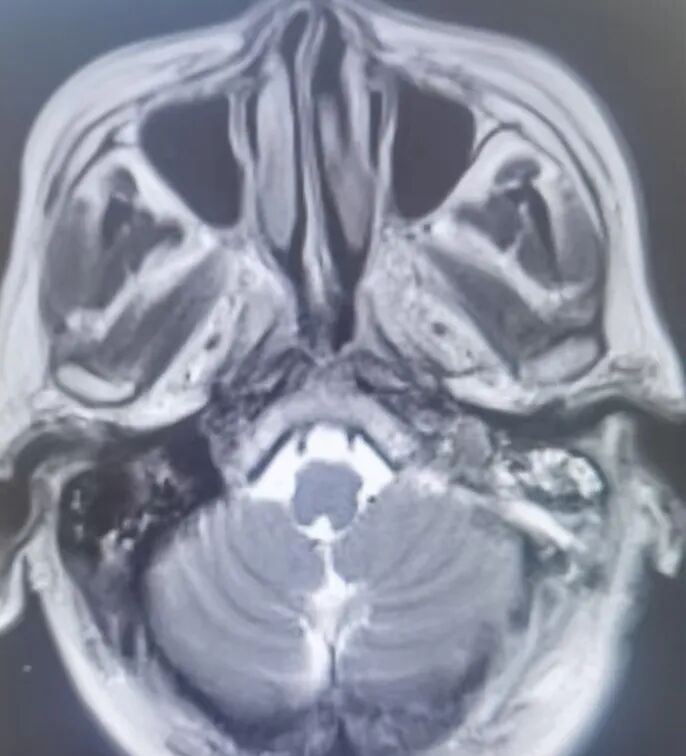

原来,李先生的母亲今年72岁,家住龙口市,一年前在当地医院查体,发现左侧桥小脑角区占位病变,诊断为“听神经瘤”,肿瘤小于2cm,医生建议观察1年后复查。1月前,老人出现了左耳听力下降的临床症状,复查颅脑核磁发现肿瘤有明显生长!

因肿瘤起源于神经的鞘膜,压迫面听神经,术中保留面听神经功能显得尤为重要。手术由耿素民教授亲自主刀,在我院神经外科团队的配合下,术中应用显微镜和神经内镜双镜联合辅助,不磨除内听道骨质便成功将肿瘤全部切除,并完好保留了面听神经功能。

应用双镜联合显微手术切除听神经瘤的优势为: 1.在不磨除内听道情况下,应用神经内镜可观察内听道内全部肿瘤,避免了手术盲区;

3.切除肿瘤后可观察内听道全程情况,避免肿瘤残留,更好地辨认神经走行;